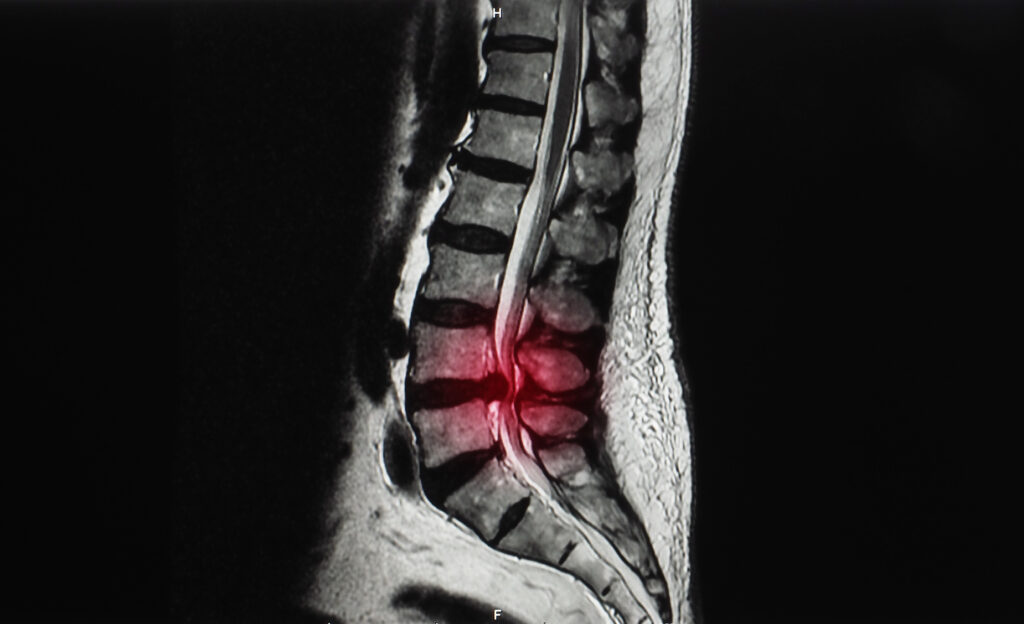

Líkaminn - verkir, einkenni o.fl. Hryggþrengsli – orsakir, einkenni og meðferðarúrræði Samkvæmt hefðbundnum læknisfræðilegum heitum er fyrirbærið hryggþrengsli (e. Spinal stenosis) allra jafna lýst sem óeðlilegum…adminágúst 28, 2023

Líkaminn - verkir, einkenni o.fl. Verkur í mjóbaki – orsakir, einkenni og meðferðir Mjóbakið er vægast sagt stórkoslegt fyrirbæri, sterkt og sveigjanlegt og gegnir lykilhlutverki fyrir heilsu okkar.…adminseptember 17, 2023

Líkaminn - verkir, einkenni o.fl. Mjóbaksverkir hjá eldra fólki – Einkenni og orsakir Eldra fólk getur vissulega fundið til hinna ýmsu verkja og einkenna sem einnig geta hrjáð…adminágúst 15, 2023